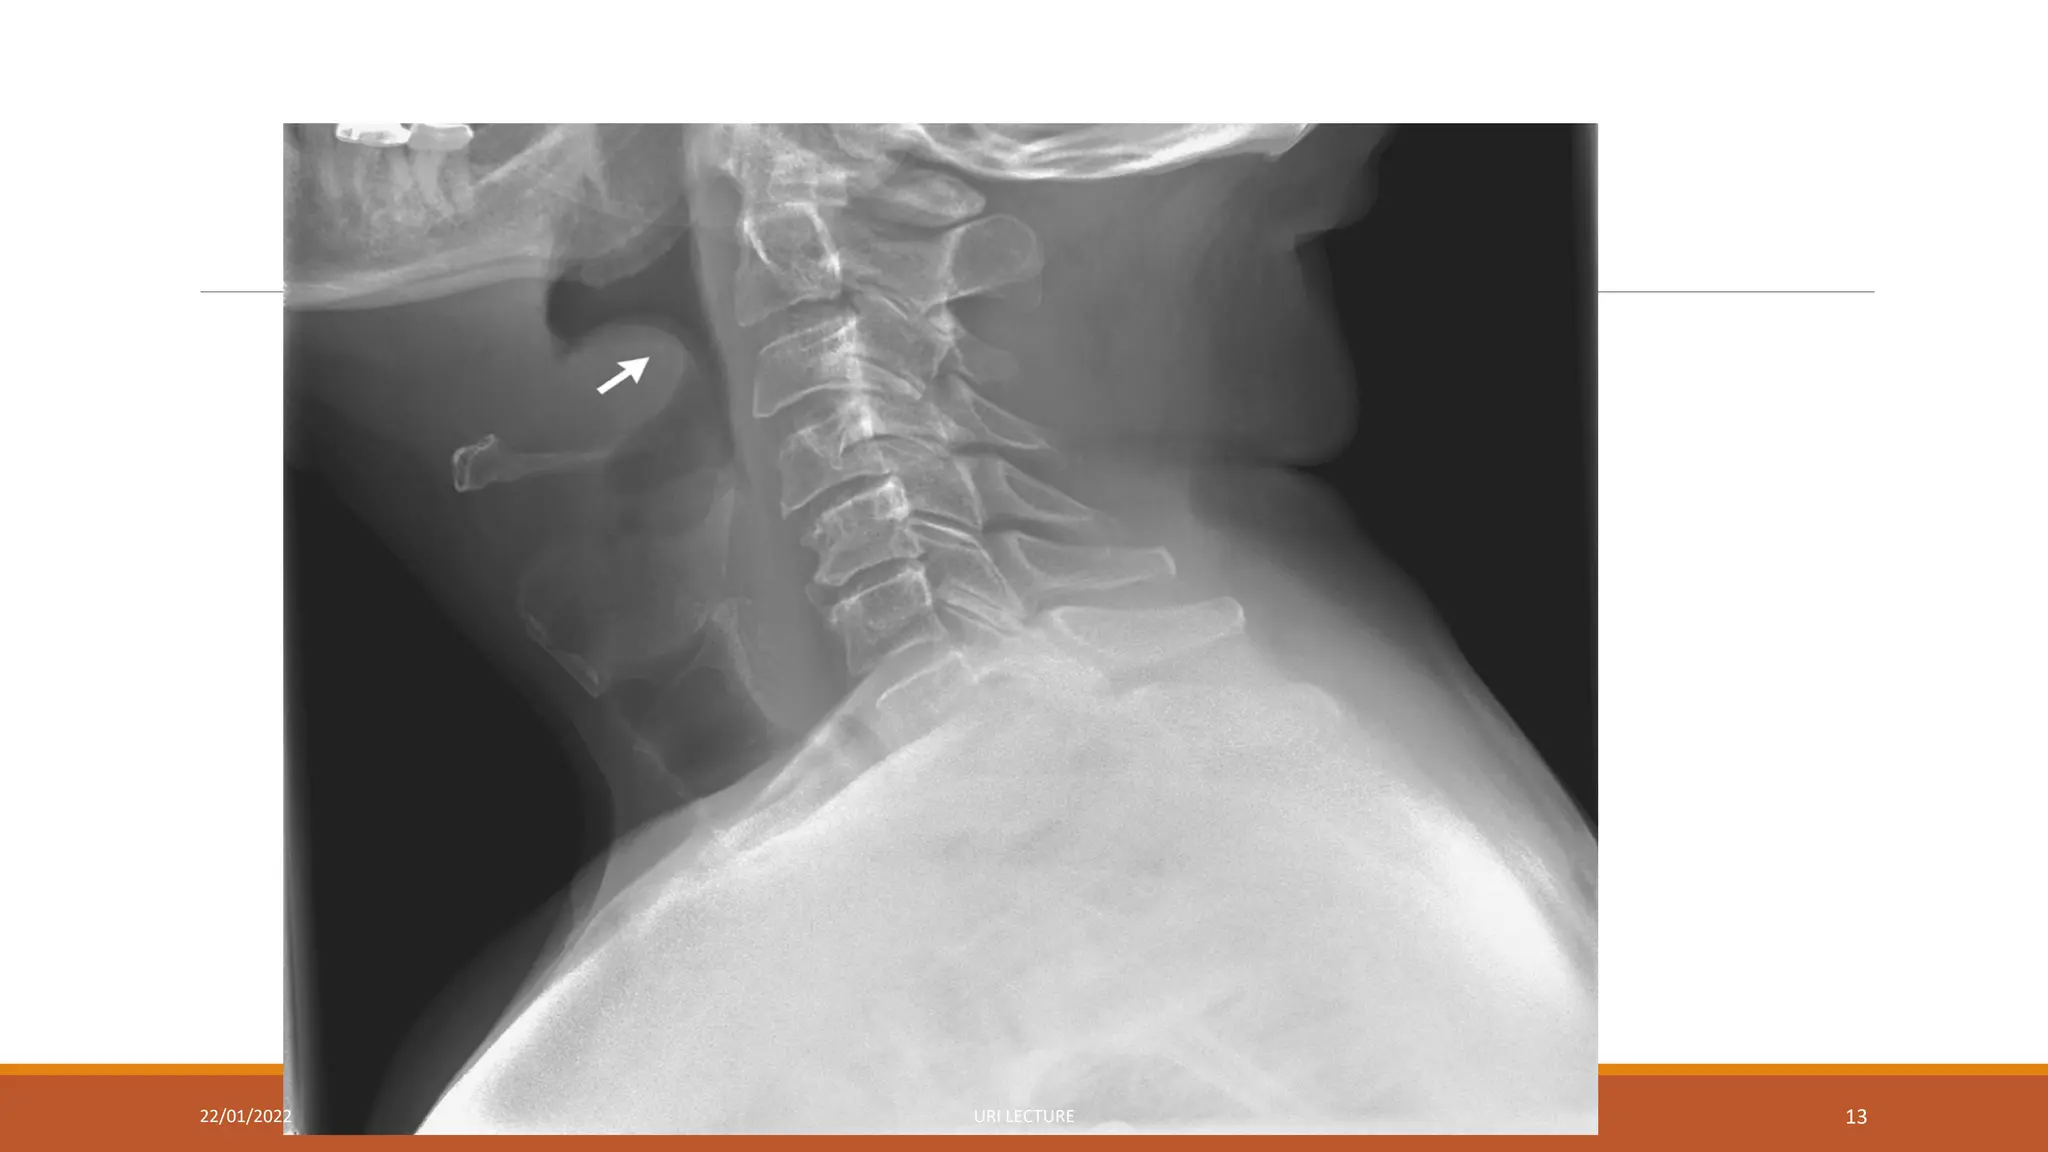

Diagnosis of LTB

The diagnosis is clinical

X-rays may show the typical subglottic narrowing

Diagnosis of LTB Thediagnosis is clinical X-rays may show the typical subglottic narrowing 22/01/2022 URI LECTURE 31

• 31.